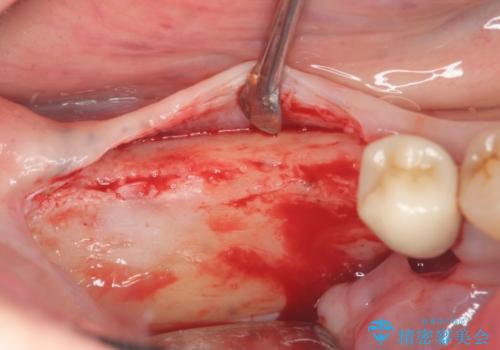

骨の造成を同時に行うインプラント治療

骨は薄くなってしまい、インプラントの長期的な安定を見込むには不十分でしたのでインプラントの埋入と同時に周囲にコツの造成を行う治療計画を立てます。